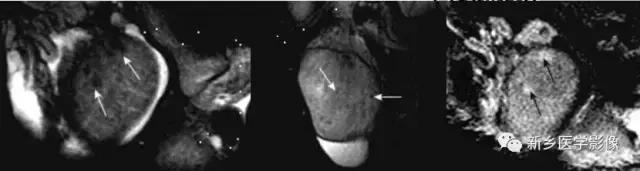

MR:*丸睾**炎T2WI不仅要低信号,增强扫描不均匀强化,合并鞘膜腔积液

MR:精原细胞瘤各信号偏低、均匀、散在,恶性病变,信号可不均;非精原细胞瘤信号不均